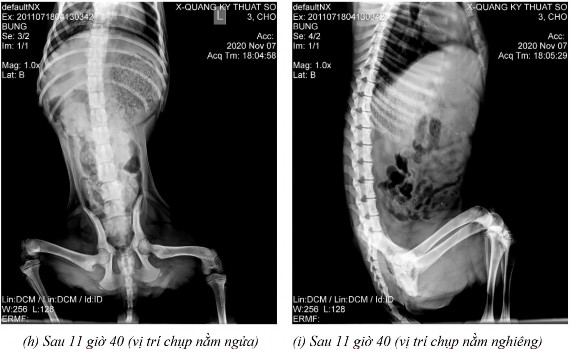

Phụ lục 5.4. Hình ảnh X-quang chó 5 ở thời điểm (a) sau 2 giờ 20 ở vị trí nằm nghiêng, (b) sau 4 giờ ở vị trí nằm ngửa, (c) sau 4 giờ ở vị trí nằm nghiêng, (d) sau 7 giờ ở vị trí nằm ngửa, (e) sau 7 giờ ở vị trí nằm nghiêng, (f) sau 9 giờ ở vị trí nằm ngửa, (g) sau 9 giờ ở vị trí nằm nghiêng, (h) sau 11 giờ 40 ở vị trí nằm ngửa và (i) sau 11 giờ 40 ở vị trí nằm nghiêng